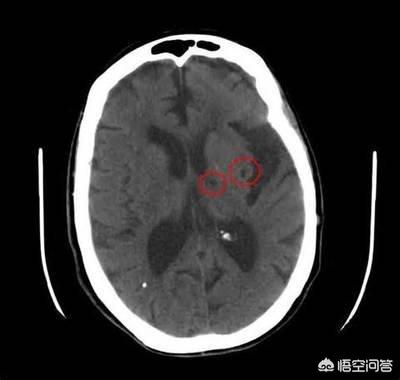

Les infarctus cérébraux caverneux sont des micro-infarctus ischémiques survenant dans la substance blanche profonde des hémisphères cérébraux et du tronc cérébral. Les foyers d'infarctus sont irrégulièrement arrondis, ovoïdes ou étroitement allongés et mesurent généralement quelques millimètres de diamètre. Dans le passé, ce phénomène n'était détecté que lors de l'anatomie pathologique du cerveau humain. Les techniques de tomodensitométrie et de résonance magnétique étant devenues plus courantes et plus avancées, la probabilité de détecter des infarctus cérébraux lacunaires a augmenté.

L'affirmation selon laquelle un infarctus caverneux est un infarctus cérébral a effrayé un grand nombre de personnes qui, à l'occasion d'un scanner ou d'une IRM de la tête, ont constaté la présence d'infarctus caverneux uniques ou multiples, ce qui a entraîné l'administration d'aspirine, de statines, etc. Est-il vraiment nécessaire de s'occuper de ces foyers d'infarctus qui ne mesurent que quelques millimètres ?

En fait, à proprement parler, l'infarctus cérébral lacunaire est un petit foyer d'infarctus formé lorsque les petites artères pénétrantes de la partie profonde des hémisphères cérébraux ou du tronc cérébral subissent une occlusion de la lumière vasculaire en raison de l'implication de divers facteurs de risque à long terme, en particulier l'effet de l'hypertension. Pour faire une analogie, si le cerveau est une feuille de papier blanc, l'infarctus cérébral lacunaire est une graine de sésame saupoudrée sur le papier blanc, très petite, mais qui existe déjà.